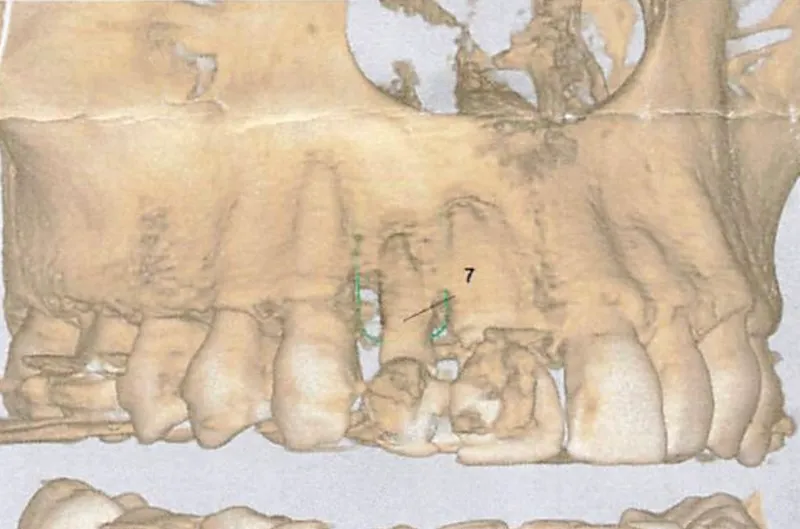

3D Imaging

We map bone density, nerve pathways, and surrounding structures. This is the foundation for everything.

Digital planning

We determine exactly where your tooth needs to sit — for proper function and natural aesthetics.

Surgical guide

The planned position is translated into a precision guide that directs placement during surgery.

No estimation — the thinking is done beforehand.